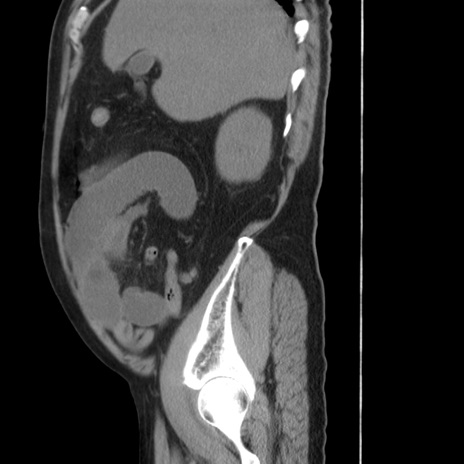

症例20(矢状断像)

【症例】 60歳代男性

【主訴】 腹部膨満、嘔吐

【現病歴】5日前頃より倦怠感を認め食事量減少し4日前の朝嘔吐、食事摂取困難となった。 3日前近医受診し点滴施行され整腸剤などを処方された。 当日他院を受診し、腹部膨満著明、炎症反応の上昇(CRP10.8、WBC11200)あり、紹介受診となる。

【身体所見】 意識JCS1 受け答えがはっきりしないBP 111/57mHg、 P 67bpm、、BT35.2°C、SpO2 97%(RA)、 腹部:膨隆、打診で鼓音あり、全体的に圧痛有り、腸蠕動音(-)、反跳痛ははっきりせず。

【データ】WBC 11400、CRP 14.20